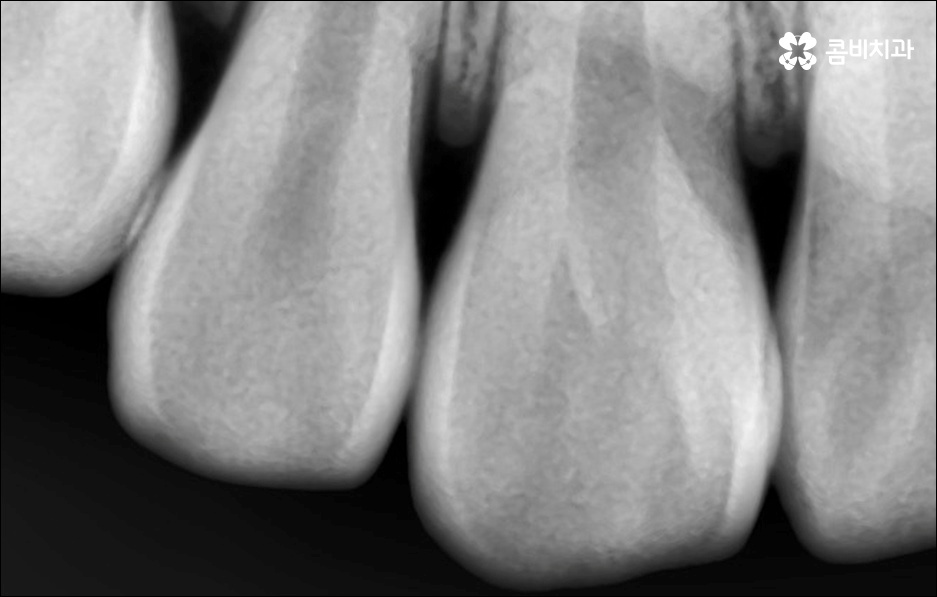

하지만 보통은 돌출된 앞니 뿐 만 아니라 골격적인 부분이 원인이 되는 경우가 많으며 이런 경우에는 상태에 맞게 전체적으로 교정을 진행하여야 교합이 올바르게 되고 입매가 전체적으로 균형감 있게 개선될 수 있어요. 이런 경우에 골격적인 원인을 무시한 채 무리하게 치아의 각도만 안쪽으로 넣으려고 하면 자칫 옥니가 될 수도 있기 때문에 이러한 부작용을 막기 위해서도 환자분들의 상황을 정확하게 검진하고 그에 맞는 교정 플랜을 세우는 것이 필요한 거예요. 물론 부정교합 정도가 심각하고 골격적인 원인이 이미 굳어진 경우와 같이 수술이 함께 필요한 케이스도 있을 수 있으나 교정 치료만으로도 튀어나온 앞니가 들어가면서 자연스럽고 부드러운 인상으로 바뀌는 경우도 많으니 먼저 검진과 상담부터 꼼꼼하게 진행해 보시길 권유드리고 있습니다. 특히 개개인의 치열, 교합, 잇몸 상태, 구강구조 등을 면밀하게 파악하고 그에 따른 정확한 치료 계획을 수립할 수 있는 경험 많은 의료진과 함께 하는 것이 중요할 수 있어요.

골격적인 부분이 원인이 되는 경우 치료 시기 역시 중요할 수 있는데요. 성장기가 끝나고 잇몸뼈가 굳어지기 전에 상악과 하악의 균형잡힌 발달을 유도하는 것이 필요하기 때문에 윗턱에 비해 아래턱이 많이 작다면 2차 성징이 나타나기 전에 치료를 시작하는 것이 좋을 거예요. 2차 성장 시기는 성별 (여자 아이가 남자 아이보다 빠름) 및 개인마다 차이가 나지만 보통 10~12세 사이이니 필요하다면 이때 아이와 함께 치과에 내원하시길 추천드리고 있는데요. 돌출입 구조에 있어서 유전의 영향은 30% 정도이니 만약에 부모님께서 상악골이 돌출된 부정교합을 가지고 있다면 더욱 관심을 가지고 아이의 치열을 관찰하셔서 치료 시기를 조율해 보시는 게 좋을 거예요. 또한 상황에 따라 교정 치료 전에 충치나 잇몸을 먼저 치료하는 과정이 필요할 수 있으니 시작 시기나 전체 기간, 방법 등 자세한 사항들에 대해서 면밀한 검진 후 충분하게 상담부터 받아 보시길 권유드리고 있습니다.